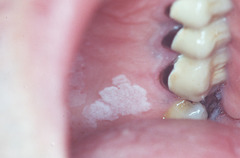

white patches on oral mucosa that can NOT be wiped off a)leukoplakia b)leukoedema c)pseudomembranous candidiasis d)candida albicans e)nicotinic stomatitis

Front

Leukoplakia

Back